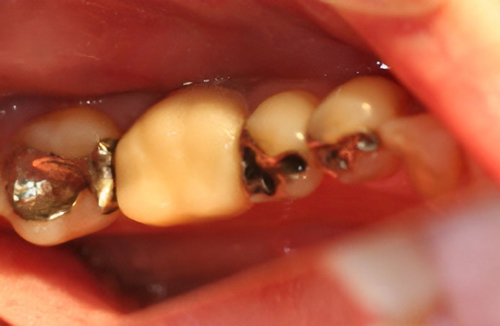

救歯MTM

虫歯が大きくて残せない歯、転倒などの事故により歯が根の深いとこで折れてしまったなどで、抜かざるを得ない歯を、骨の中に埋まっている健全な根を、骨の上に矯正的に引き上げることで、その歯を抜かず温存、救歯できる可能性のある治療方法です。

また、救歯BTAセラミックは、BTAテクニック®が持つ成功する理由(*)から、深い位置まで虫歯が進行してしまって歯を抜かないとならない歯に応用する事で、抜かずに治療することが出来る場合がある。

症例によっては、BTAテクニック® , 救歯セラミックが適応出来ない場合があります。 また、この方法を用いることで必ず歯が残せるという治療方法ではありません。